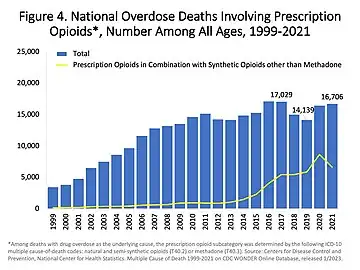

Each year 69,000 people worldwide die of opioid overdose, and 15 million people have an opioid addiction.[65]

According to the USCDC, methadone was involved in 31% of opioid related deaths in the US between 1999–2010 and 40% as the sole drug involved, far higher than other opioids.[71] Studies of long term opioids have found that many stop them, and that minor side effects were common.[72] Addiction occurred in about 0.3%.[72] In the United States in 2016 opioid overdose resulted in the death of 1.7 in 10,000 people.[73]

Opioid prescriptions in the US increased from 76 million in 1991 to 207 million in 2013.[185]

In the 1990s, opioid prescribing increased significantly. Once used almost exclusively for the treatment of acute pain or pain due to cancer, opioids are now prescribed liberally for people experiencing chronic pain. This has been accompanied by rising rates of accidental addiction and accidental overdoses leading to death. According to the International Narcotics Control Board, the United States and Canada lead the per capita consumption of prescription opioids.[186] The number of opioid prescriptions per capita in the United States and Canada is double the consumption in the European Union, Australia, and New Zealand.[187] Certain populations have been affected by the opioid addiction crisis more than others, including First World communities[188] and low-income populations.[189] Public health specialists say that this may result from the unavailability or high cost of alternative methods for addressing chronic pain.[190] Opioids have been described as a cost-effective treatment for chronic pain, but the impact of the opioid epidemic and deaths caused by opioid overdoses should be considered in assessing their cost-effectiveness.[191] Data from 2017 suggest that in the U.S. about 3.4 percent of the U.S. population are prescribed opioids for daily pain management.[192] Calls for opioid deprescribing have led to broad scale opioid tapering practices with little scientific evidence to support the safety or benefit for patients with chronic pain.

The release of OxyContin in 1996 was accompanied by an aggressive marketing campaign promoting the use of opioids for pain relief. Increasing prescription of opioids fueled a growing black market for heroin. Between 2000 and 2014 there was an "alarming increase in heroin use across the country and an epidemic of drug overdose deaths".[237][211][238]

As a result, health care organizations and public health groups, such as Physicians for Responsible Opioid Prescribing, have called for decreases in the prescription of opioids.[237] In 2016, the Centers for Disease Control and Prevention (CDC) issued a new set of guidelines for the prescription of opioids "for chronic pain outside of active cancer treatment, palliative care, and end-of-life care" and the increase of opioid tapering.[239]

In 2011, the Obama administration released a white paper describing the administration's plan to deal with the opioid crisis. The administration's concerns about addiction and accidental overdosing have been echoed by numerous other medical and government advisory groups around the world.[190][245][246][247]

As of 2015, prescription drug monitoring programs exist in every state, except for Missouri.[248] These programs allow pharmacists and prescribers to access patients' prescription histories in order to identify suspicious use. However, a survey of US physicians published in 2015 found that only 53% of doctors used these programs, while 22% were not aware that the programs were available to them.[249] The Centers for Disease Control and Prevention was tasked with establishing and publishing a new guideline, and was heavily lobbied.[250] In 2016, the United States Centers for Disease Control and Prevention published its Guideline for Prescribing Opioids for Chronic Pain, recommending that opioids only be used when benefits for pain and function are expected to outweigh risks, and then used at the lowest effective dosage, with avoidance of concurrent opioid and benzodiazepine use whenever possible.[34] Research suggests that the prescription of high doses of opioids related to chronic opioid therapy (COT) can at times be prevented through state legislative guidelines and efforts by health plans that devote resources and establish shared expectations for reducing higher doses.[251]

On 10 August 2017, Donald Trump declared the opioid crisis a (non-FEMA) national public health emergency.[252]